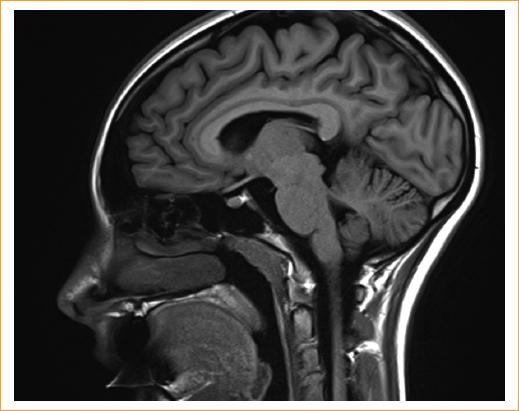

Se presenta el caso de una mujer de 18 años con antecedentes familiares migrañosos valorada por un oftalmólogo por presentar visión borrosa, fotofobia, fonofobia y una intensa cefalea pulsátil en toda la cabeza en agosto de 2019. En la exploración inicial, la paciente presentó midriasis bilateral con un diámetro de 5,0 mm en ambas pupilas (Fig. 1). En ninguna de las dos pupilas hubo reflejo pupilar directo ni consensual a la luz. Además, en ambas pupilas pudo acreditarse una pérdida completa de acomodación visual. La paciente dijo no utilizar colirio. Se descartó la presencia de ptosis y compromiso ocular. La exploración del fondo de ojo condujo a un diagnóstico de edema papilar en ojo derecho con ojo izquierdo sin hallazgos (Fig. 2). Algunos días después, se realizó la prueba de campo visual de Humphrey (HVF) y una OCT del nervio óptimo. Los resultados de ambas pruebas fueron normales. Ese mismo día, la paciente fue valorada por un neurólogo. La exploración neurológica basal también fue normal. Para descartar neoplasia o afectación vascular, se realizaron sendas IRM (Fig. 3) y ARM (Fig. 4). Los resultados de estas dos pruebas diagnósticas también fueron normales en ausencia de una masa aparente, afectación vascular ni señales de presión intracraneal elevadas. Tanto la prueba de la enfermedad de Lyme como la de anticuerpos antinucleares dieron negativo. La prueba de electroquimioluminiscencia que se realizó para determinar cualitativamente la presencia de anticuerpos totales (IgM, IgG) contra Treponema pallidum también dio negativo. La tasa de sedimentación eritrocítica, la prueba para determinar los niveles de lactato total en sangre, la prueba de la proteína C reactiva y la prueba de procalcitonina fueron, también, normales. Por último, se realizó un análisis toxicológico que dio negativo a cualquier sustancia que la paciente pudiese haber consumido.